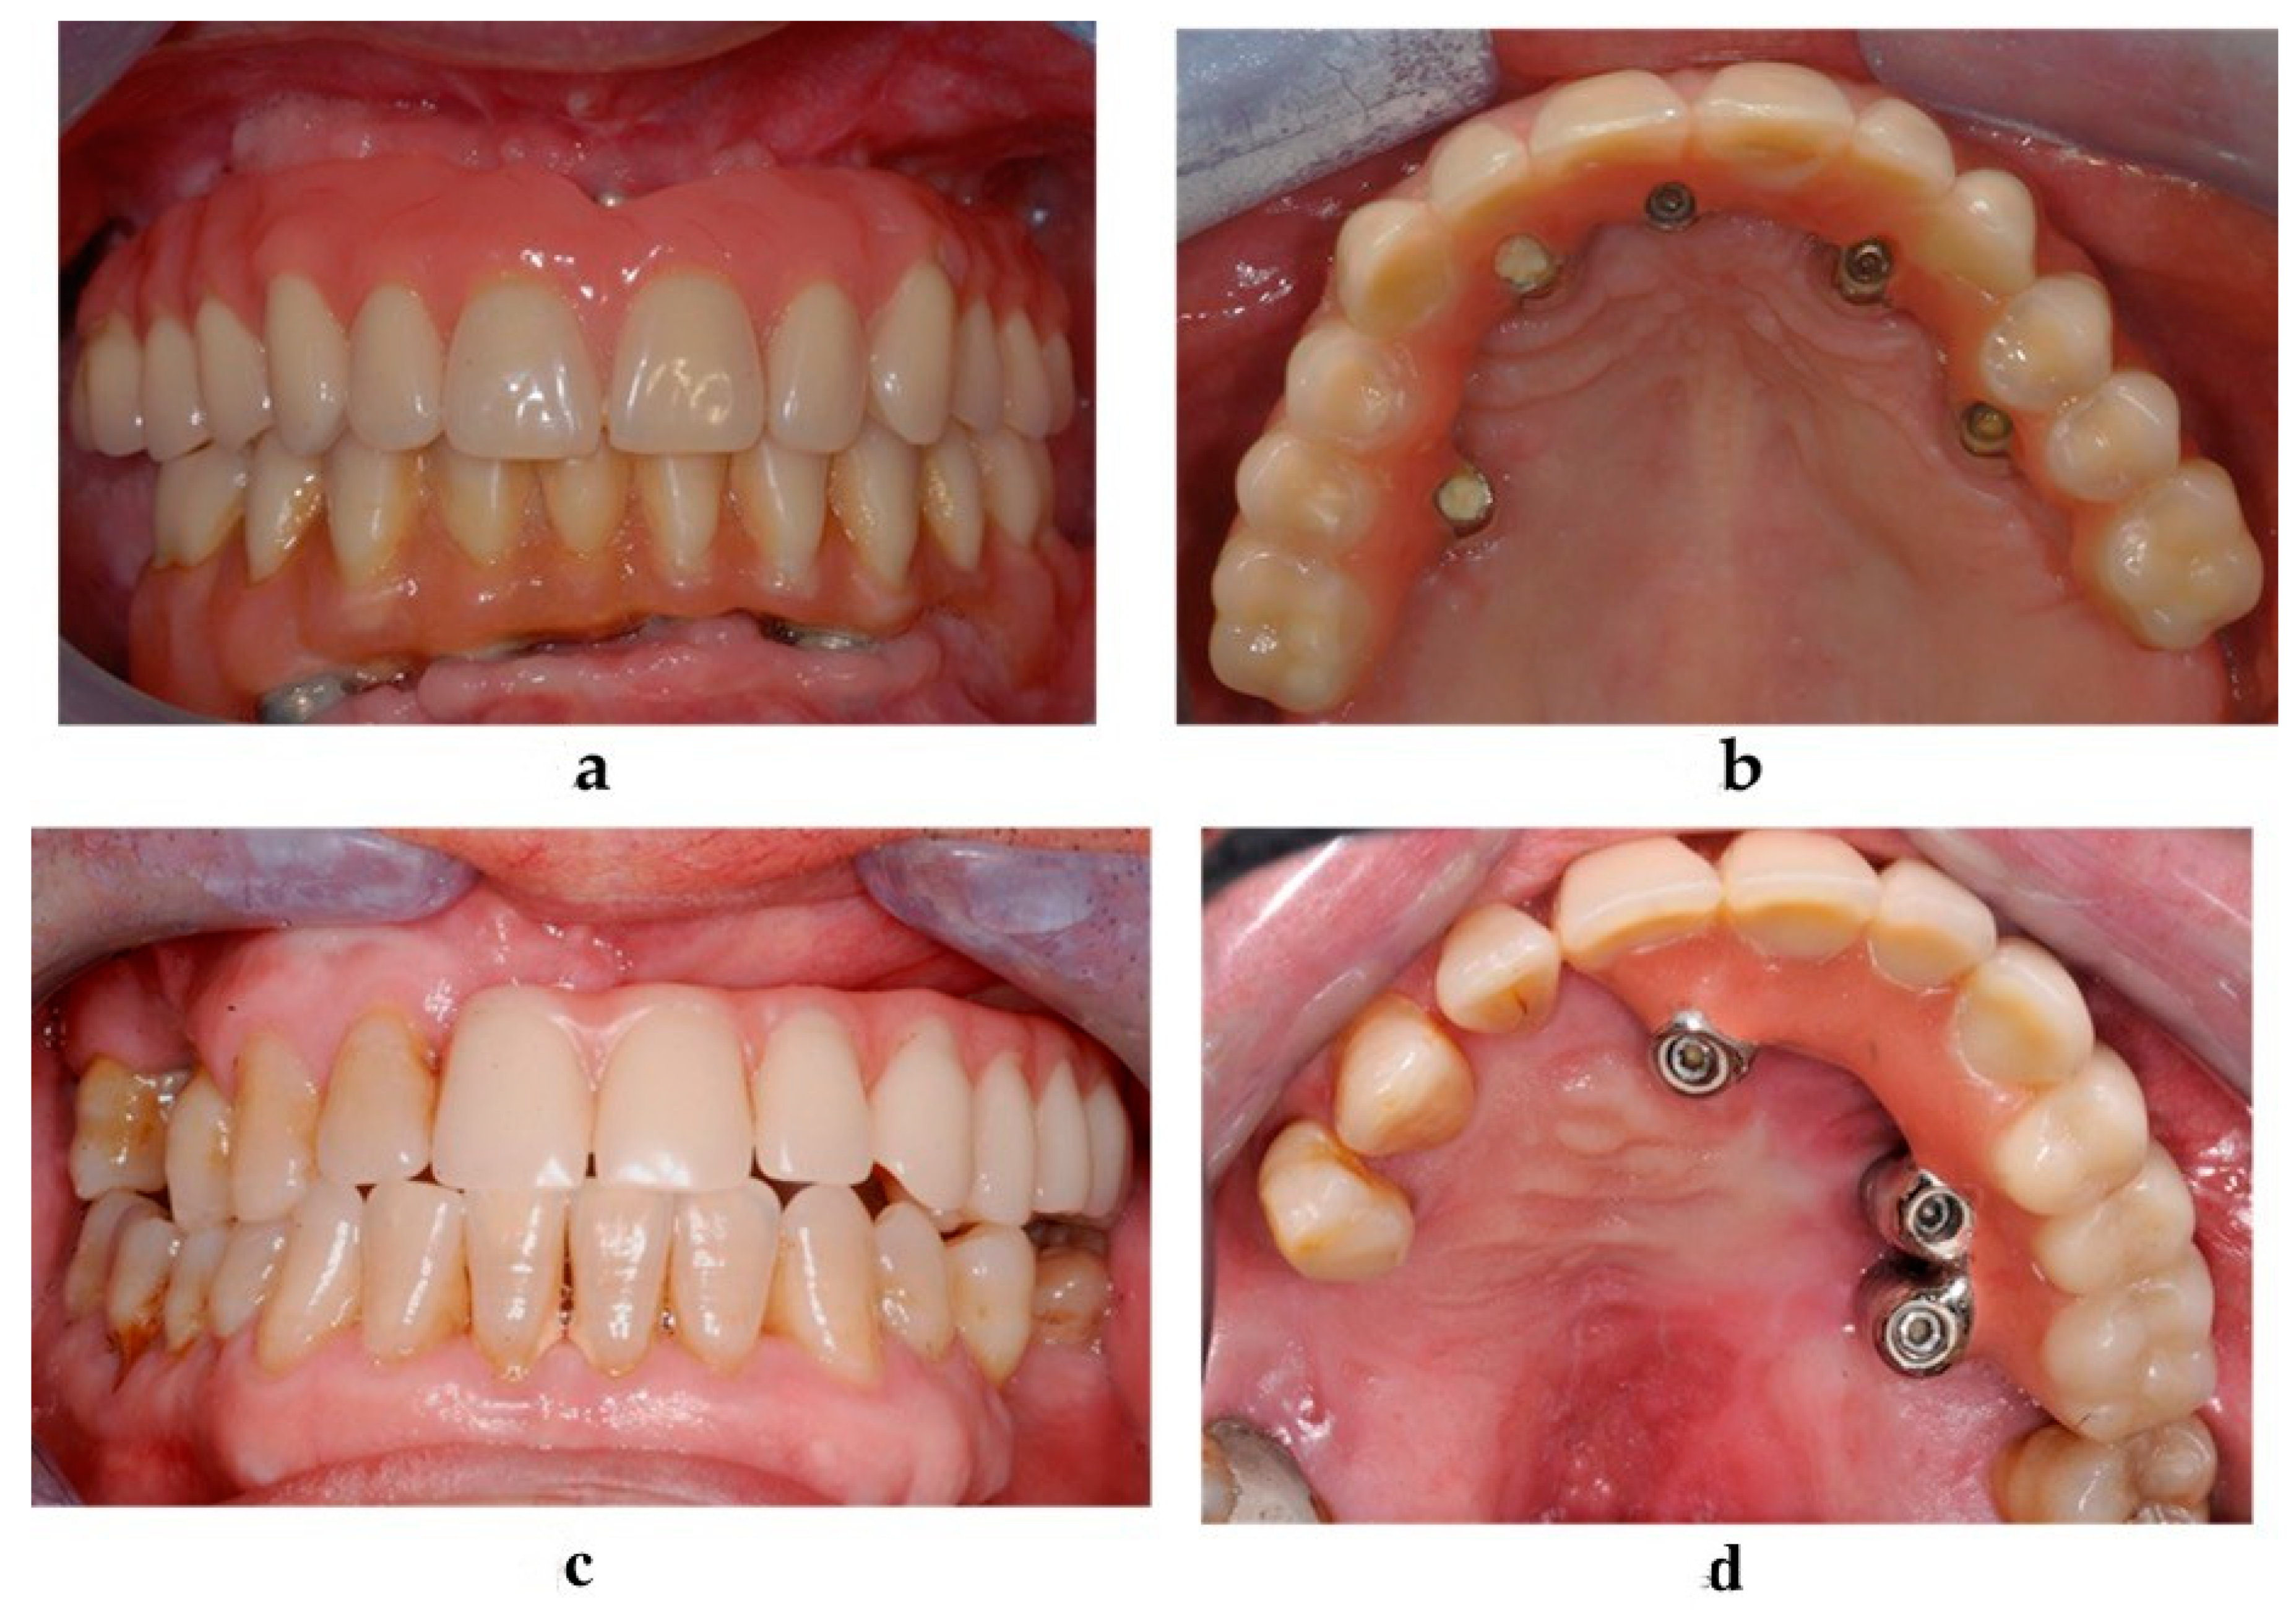

A maxillofacial type navigation system involving the use of an extraoral reference tool (onto the cranial bone) was employed in three oncologic patients in whom the residual maxillary bone was not sufficient for the fixing of the intraoral reference tool. After a final evaluation carried out by a depth gauge, zygomatic implants (Southern Implants, Irene, South Africa) were positioned via the use of implant motor or manually using a fixture mount. Standard zygomatic implants were placed in patients from the atrophic group and in oncologic patients when the implant collar was surrounded by the residual crestal bone (Figure 2a). The oncologic type of zygomatic implant was placed when there was only soft tissue around the implant collar (Figure 2b).

Figure 2. The zygomatic implant was placed and the conical abutment was screwed before suturing. (a) The standard type of zygomatic implant was used for patients with maxillary atrophy. (b) An oncologic type of zygomatic implant with a machined coronal part was used for implant sites that lacked crestal bone.

Figure 4. Clinical evaluation and soft tissue maintenance in the atrophic group (a,b) and in the oncologic group (c,d): frontal view (a), palatal view (b).